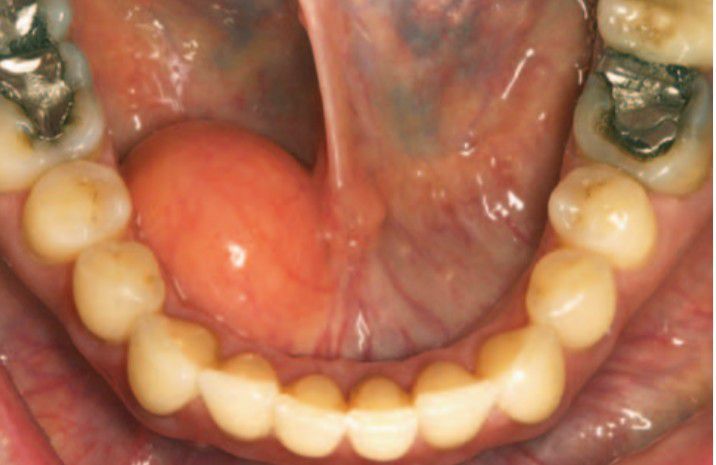

The lipoma is a benign tumor of fat. Although it represents by far the most common mesenchymal neo-plasm, most examples occur on the trunk and proximal portions of the extremities. Oral lipomas are usually soft, smooth-surfaced nodular masses that can be sessile or pedunculated.Typically, the tumor is asymptomatic and often has been noted for many months or years before diagnosis. Most are less than 3 cm in size, but occasional lesions can become much larger The picture shows soft, yellow nodular mass in the floor of the mouth.